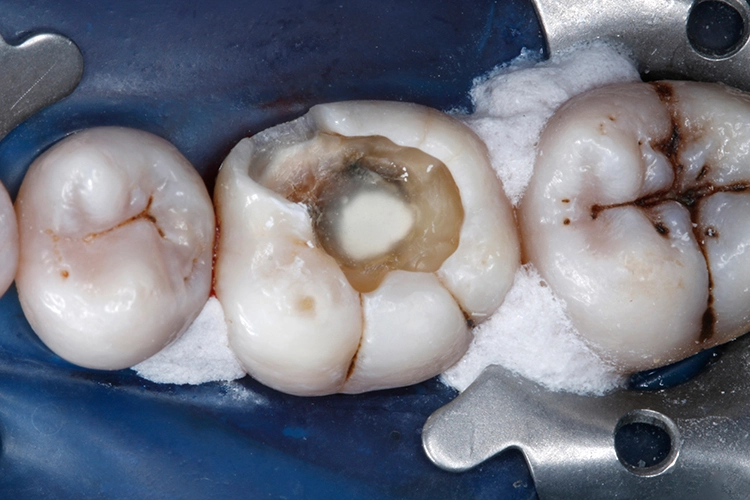

Ein 38-jähriger Patient erschien in unserer Sprechstunde mit einem frakturierten mesiolingualen Höcker neben einer okklusalen Amalgamfüllung am unteren rechten 1. Molaren (Zahn 46). Der Vorfall hatte sich bereits vor einer Woche ereignet, der Zahn war noch am selben Tag im zahnärztlichen Notdienst provisorisch mit einer Glasionomerzementfüllung versorgt worden (Abb. 1). Der Defekt erstreckte sich bis auf Höhe der marginalen Gingiva (Abb. 2).